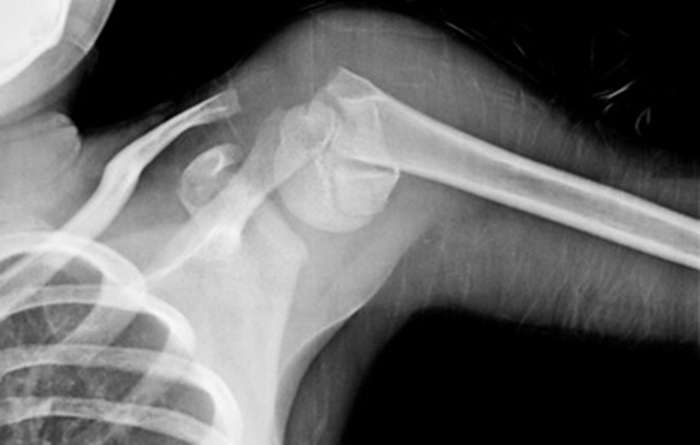

При подозрении на вывих съемку проводят в аксиальной проекции. Рука согнута в локте (ладонь вниз). Такой снимок дает возможность определить смещение головки кости относительно сумки сустава.